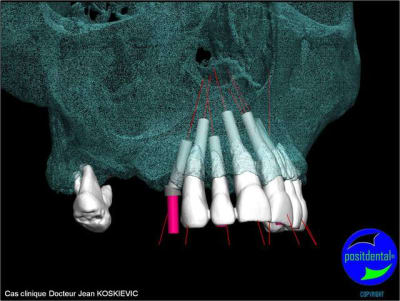

et la projet 10 implants maxillaire sup

10 en haut

donc ce sera minimum 8 en fonction du scan